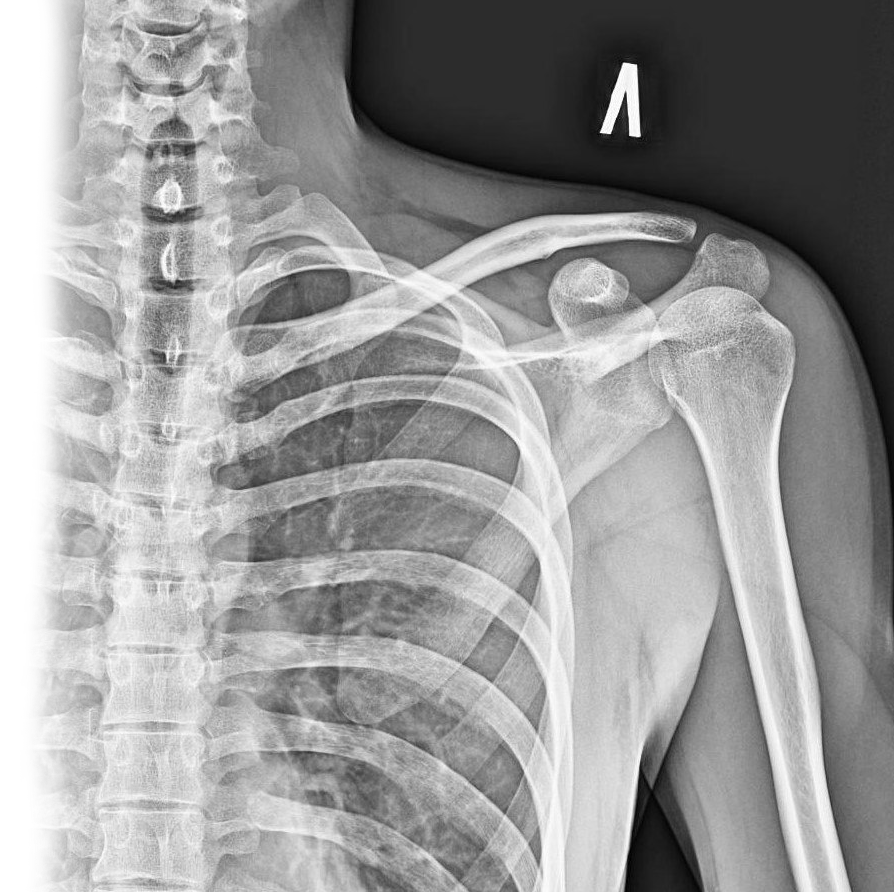

Рентгенография лопатки – важный метод прицельного исследования, который позволяет оценить состояние лопатки.

Диагностическая услуга выполняется в двух проекциях.

Рентген позволяет оценить наличие костно-травматической патологии лопатки.